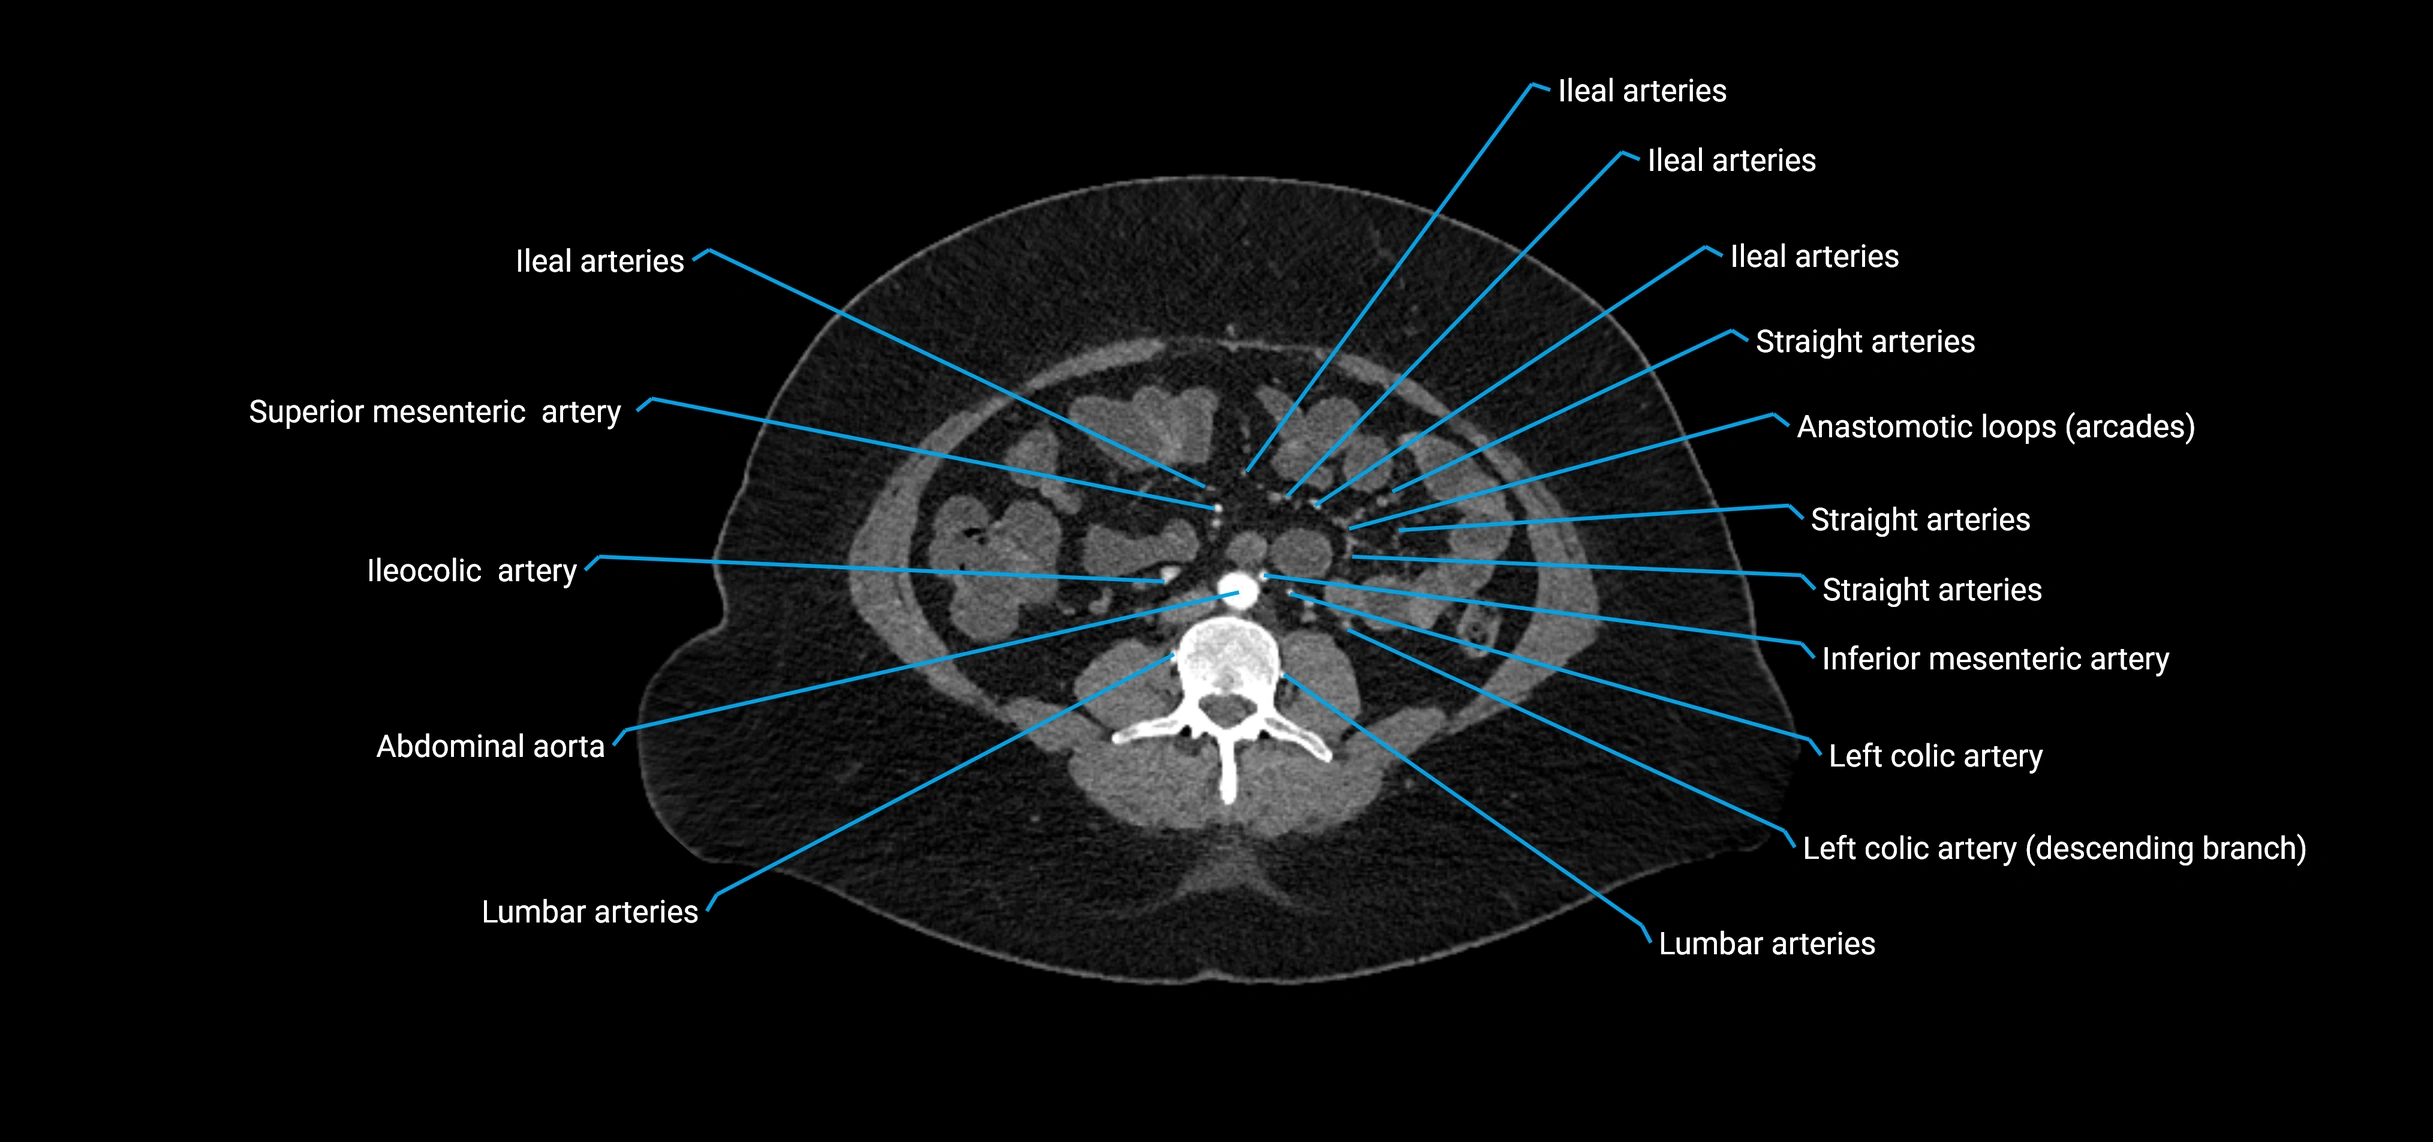

CT images

image

CT Appearance

Non-contrast CT:

• Appears as a tubular soft tissue structure anterior to vertebral bodies

• Calcified atherosclerotic plaques appear as hyperdense foci along the wall

• Useful for screening abdominal aortic aneurysm (AAA) size and mural calcification

Contrast-enhanced CT (CTA):

• Gold standard for abdominal aortic imaging

• Provides excellent detail of lumen, wall, aneurysm, thrombus, and branch vessels

• Multiplanar and 3D reconstructions help in aneurysm measurement, stent graft planning, and dissection evaluation

• Detects acute rupture, traumatic injury, or occlusion with high sensitivity